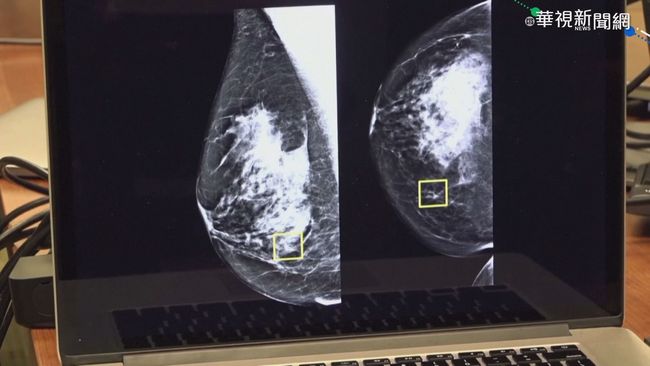

黃醫師特別說明,雖然九成乳房腫塊屬於良性,包括纖維囊腫、水泡或發炎,但一般人難以自行分辨。當腫塊大到能觸摸時,通常已接近2公分。若發現不會痛的硬塊且月經過後仍持續存在,或在腋下發現任何大小的硬塊,都必須高度警覺盡速就醫。乳房纖維囊腫常見於30至50歲女性,雖屬良性但可能與乳癌同時存在,不可輕忽。

圖片來源:華視